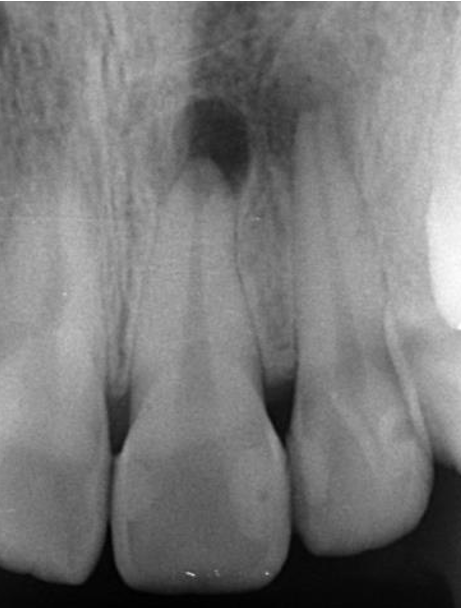

症例4

治療経過

①![]() 術前 |

②![]() 根管治療後3か月経過 |

③![]() 根管治療後1年経過時 |

④![]() 根管治療後2年経過時 |

神経の治療後、①→②→③→④と時間をかけて徐々に治ってくることがあります。

神経の治療は細菌感染を除去する治療です。細菌がいなくなれば、無駄に神経をとらなくても良い歯もあるかもしれません。

レントゲン検査や患者様の訴える症状だけでは神経を残せるかどうかは断定できません。 この方もレントゲン写真上では神経を残せないように見える歯でしたが、治療前に検査を入念に行うことで残せる可能性を見出すことができました。 同じ悩みを抱えた方は是非お気軽にご相談下さい。 |